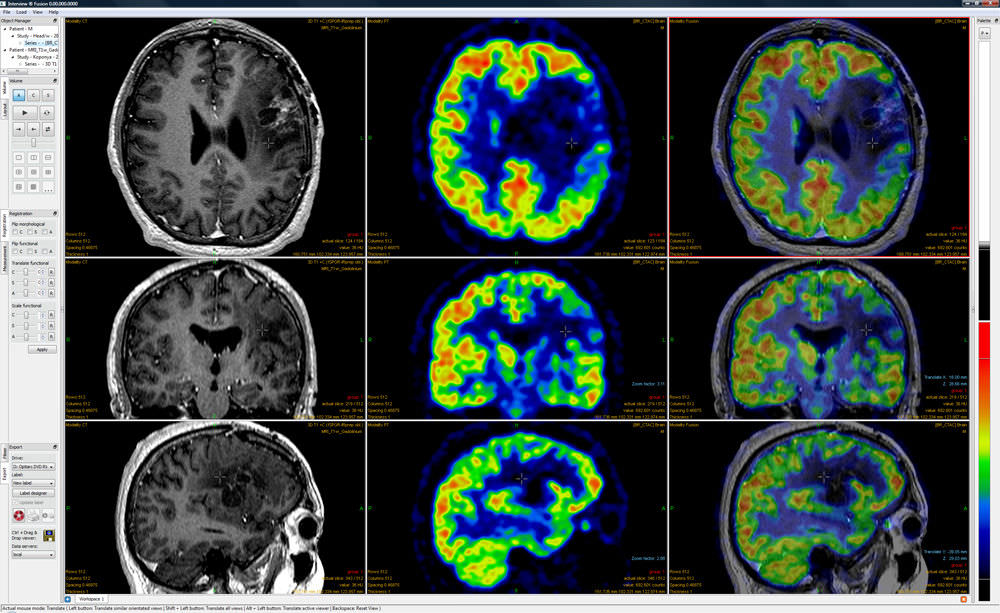

From www.medicalexpo.com

Multimodal image fusion software InterView™ FUSION Mediso medical Medical Image Fusion Using Deep Learning Github In this paper, we propose a novel deep medical image fusion method based on a deep convolutional neural network (dcnn) for. A framework for medical image segmentation with convolutional neural networks and deep learning By employing principal component analysis, grey wolf optimization, and a recurrent neural network, we have developed a novel fusion. In this paper, we describe different data. Medical Image Fusion Using Deep Learning Github.